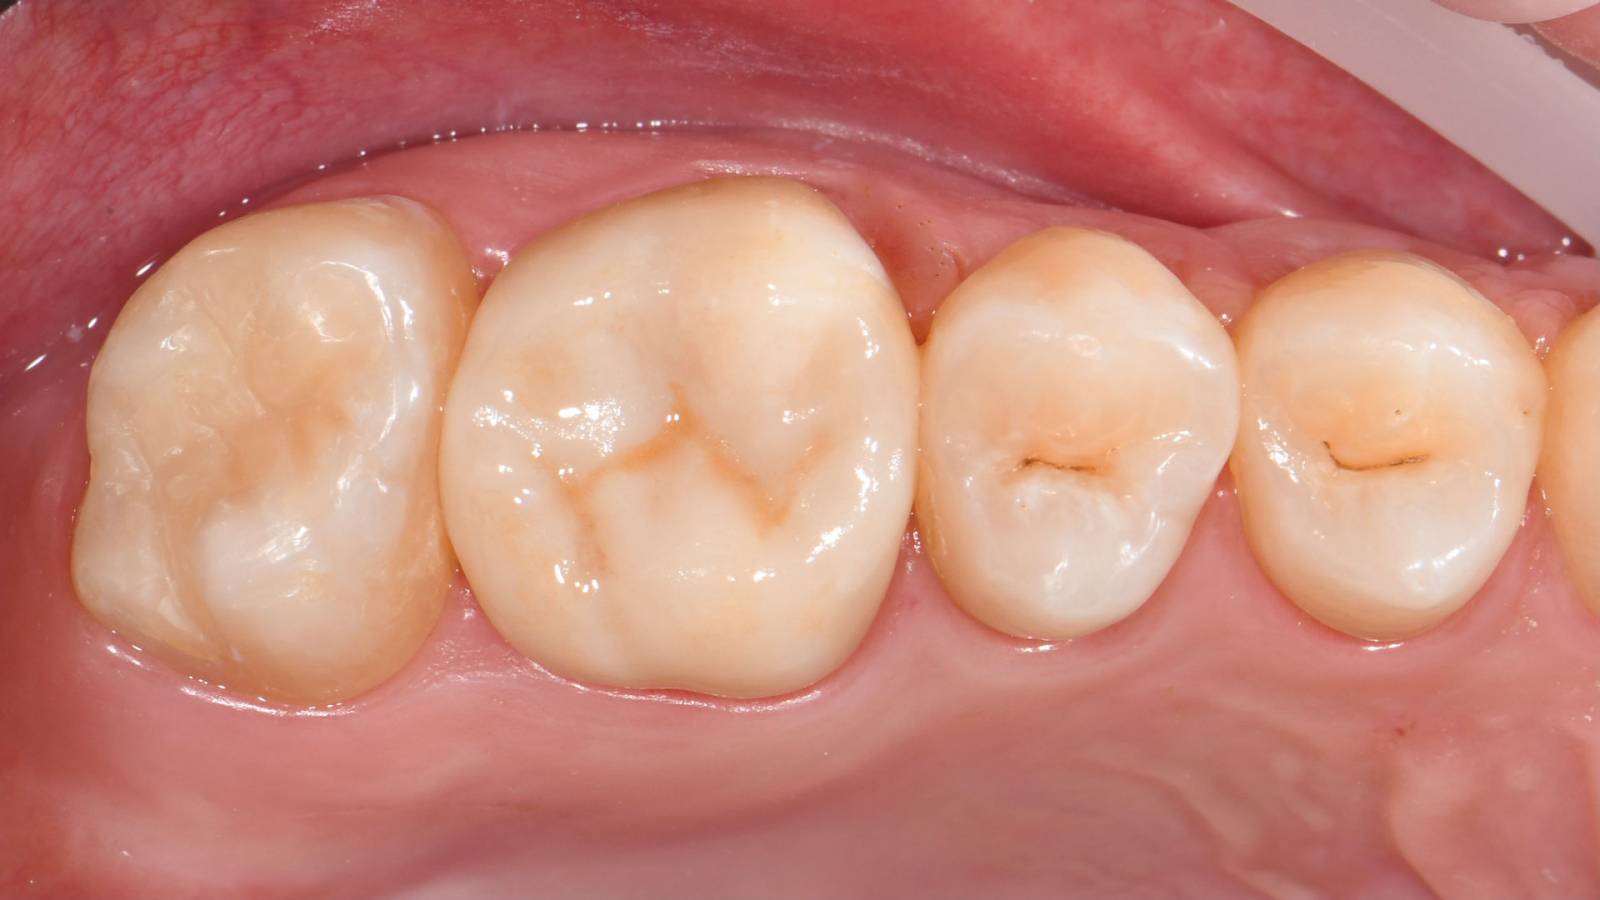

Quadrant rehabilitation

Two CEREC Tessera crowns and two inlays

Within a single visit of four hours the restoration of two crowns and two inlays, which were 15 years old, was carried out. The patient was very pleased with the very good esthetic result.

Before: Insufficient fillings in the second quadrant. The restorations were about 15 years old.

After: Chairside-fabricated crowns made from CEREC Tessera (teeth 26/27). Inlays for teeth 24 and 25 made of composite blocks.

Dr. Andreas Bindl

Zurich, Switzerland